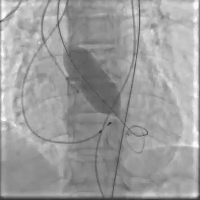

在快心室率起搏下平稳释放瓣膜,瓣膜释放过程稳定流程,瓣膜准确铆定于主动脉瓣环(视频3)。

术后造影(视频3)

停止起搏并撤回输送系统,撤出引导钢丝,关闭血管入路,术后造影及超声评价瓣膜功能良好,前向血流速度1m/s, 无明显瓣周漏(视频4)。

术后超声(视频4)